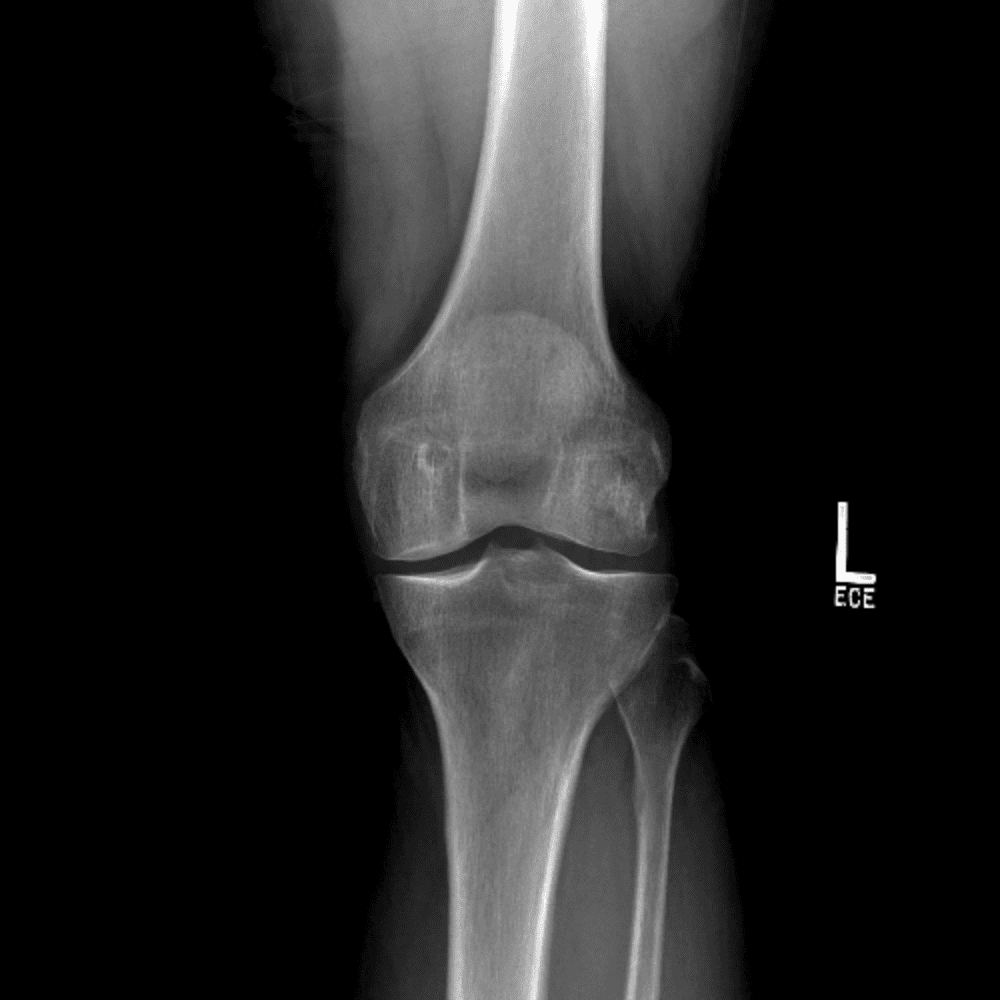

Simula o plantão incluindo casos sutis ou difíceis e alguns normais.